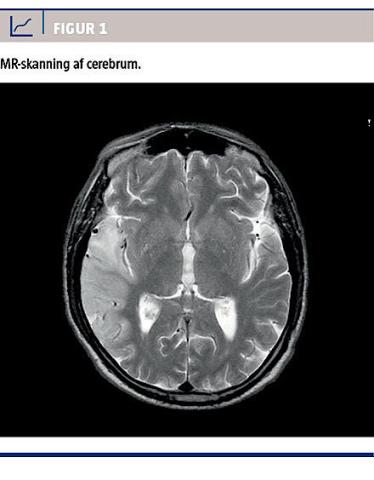

II. En 46-årig mand, der havde haft insulinbehandlet diabetes mellitus igennem 15 år (basalbolusterapi), blev indlagt efter et komplekst partielt krampeanfald. Han havde metabolisk acidose (laktatniveau: 19 mmol/l, pH-værdi: 7,1) og var neurologisk intakt fraset et kendt perceptivt høretab. Laktoacidosen ophævedes i løbet af et halvt døgn. Tre dage senere blev han genindlagt efter et lignende anfald med laktoacidose (laktatniveau: 12 mmol/l, pH-værdi: 7,2). Siden udskrivelsen havde han haft hukommelsessvækkelse, været præget af apraksi og haft usikker gangfunktion. CT af cerebrum viste forandringer i højre temporallap, hvilket tydede på nyere infarktområde, og ved MR-skanning påvistes der et højresidigt gyralt ødem temporoparietalt (Figur 1). Neurologisk fandt man nu diskret venstresidig neglect, usikker gang og balance samt lettere kognitiv påvirkning.

På baggrund af patientens diabetes, hørenedsættelse, laktoacidose og apopleksilignende tilfælde havde man mistanke om MIDD henholdsvis MELAS. Ved gennemgang af tidligere journaler fandt man, at han i 2003 fik stillet diagnosen MIDD (Figur 2) med påvisning af mtDNA3243A>G. Der blev senere fundet generaliseret muskelatrofi, og en MR-skanning

viste uændret infarktsequelae med aftagende ødem.